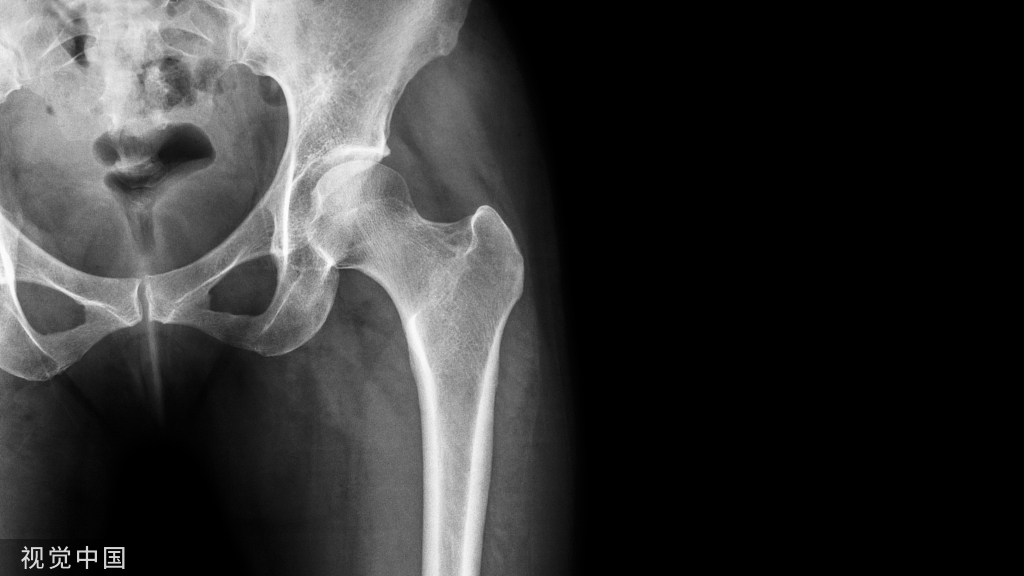

胫骨 pilon 骨折的发生多是由于高能量轴向负荷产生的关节和干骺端粉碎以及广泛的软组织损伤。腓骨骨折的存在是胫骨 pilon 骨折放射学严重程度的预测指标。